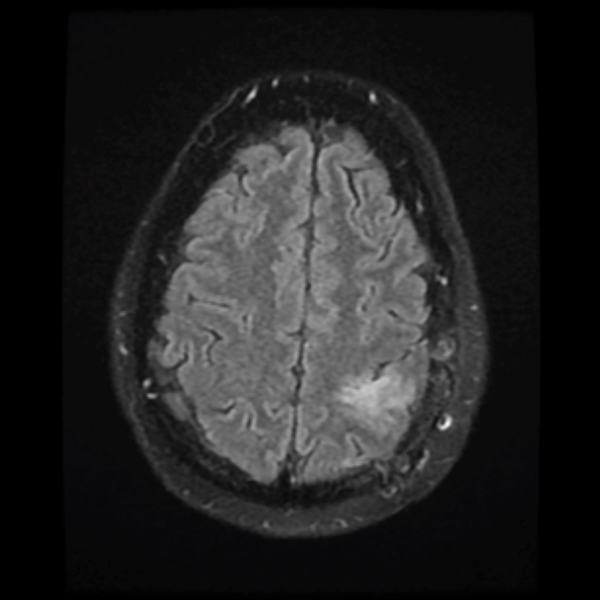

Treatment with chemotherapy and radiation under the care of Dr. Grewal resulted in a durable response of the tumor as evident in the post-treatment images.

December 2019